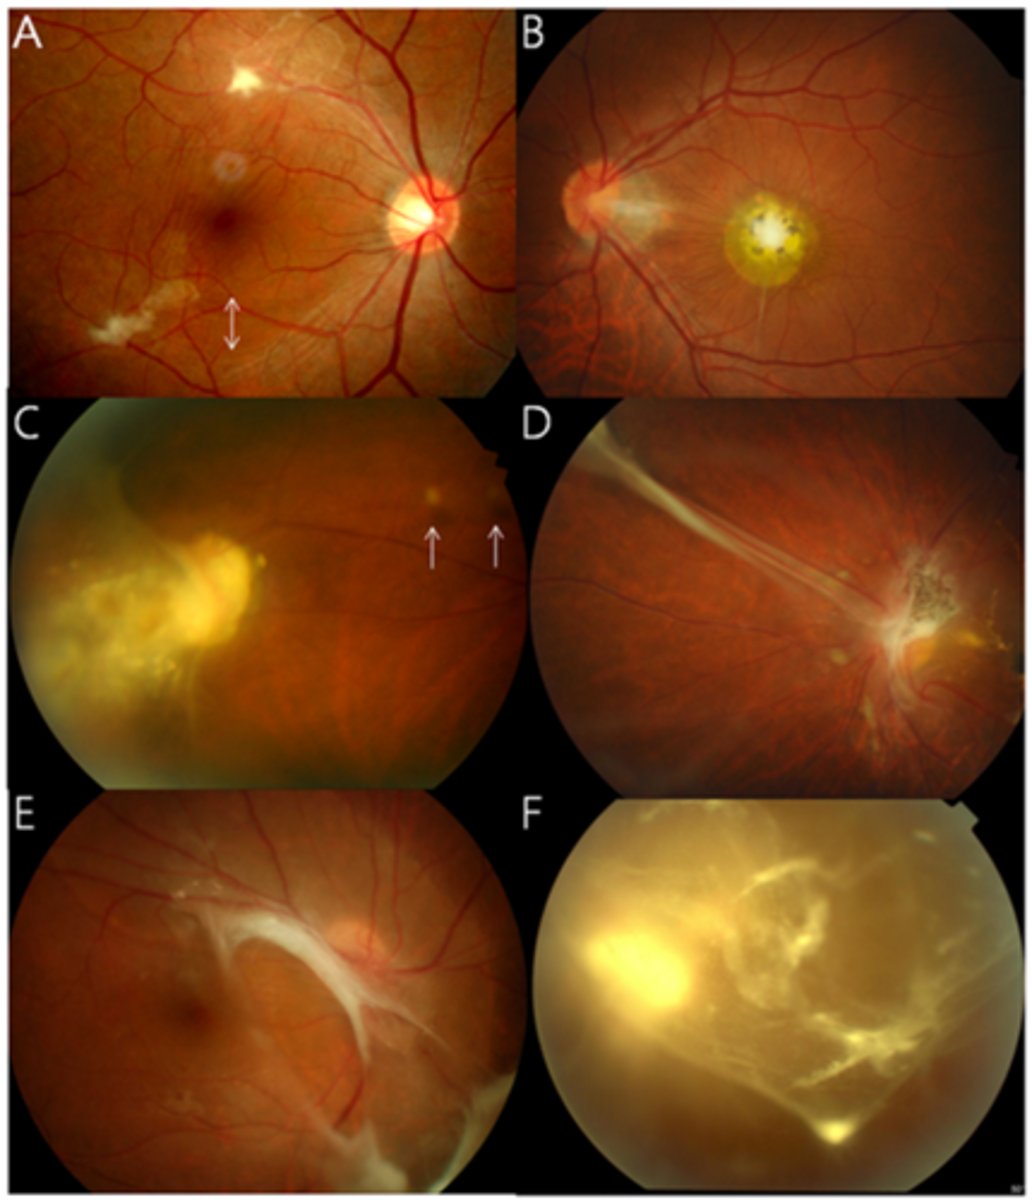

What finding of toxoplasmosis is seen in A/B?

retinitis turns into hazy scar with nerve pallor

What finding of toxoplasmosis is seen in C/D?

scarring overtime with VA loss/scotoma

What is seen in toxoplasmosis with OCT?

acute = retinitis = inflam, thickening of layers

acute = vitritis = dots and haze vitreous

chronic = necrotizing atrophy = scarring, thinning

What findings of toxoplasmosis are seen here?

retinal vasculitis

exudative scar

focal, hazy vitritis and retinitis

What findings of toxoplasmosis are seen here?

latent scars